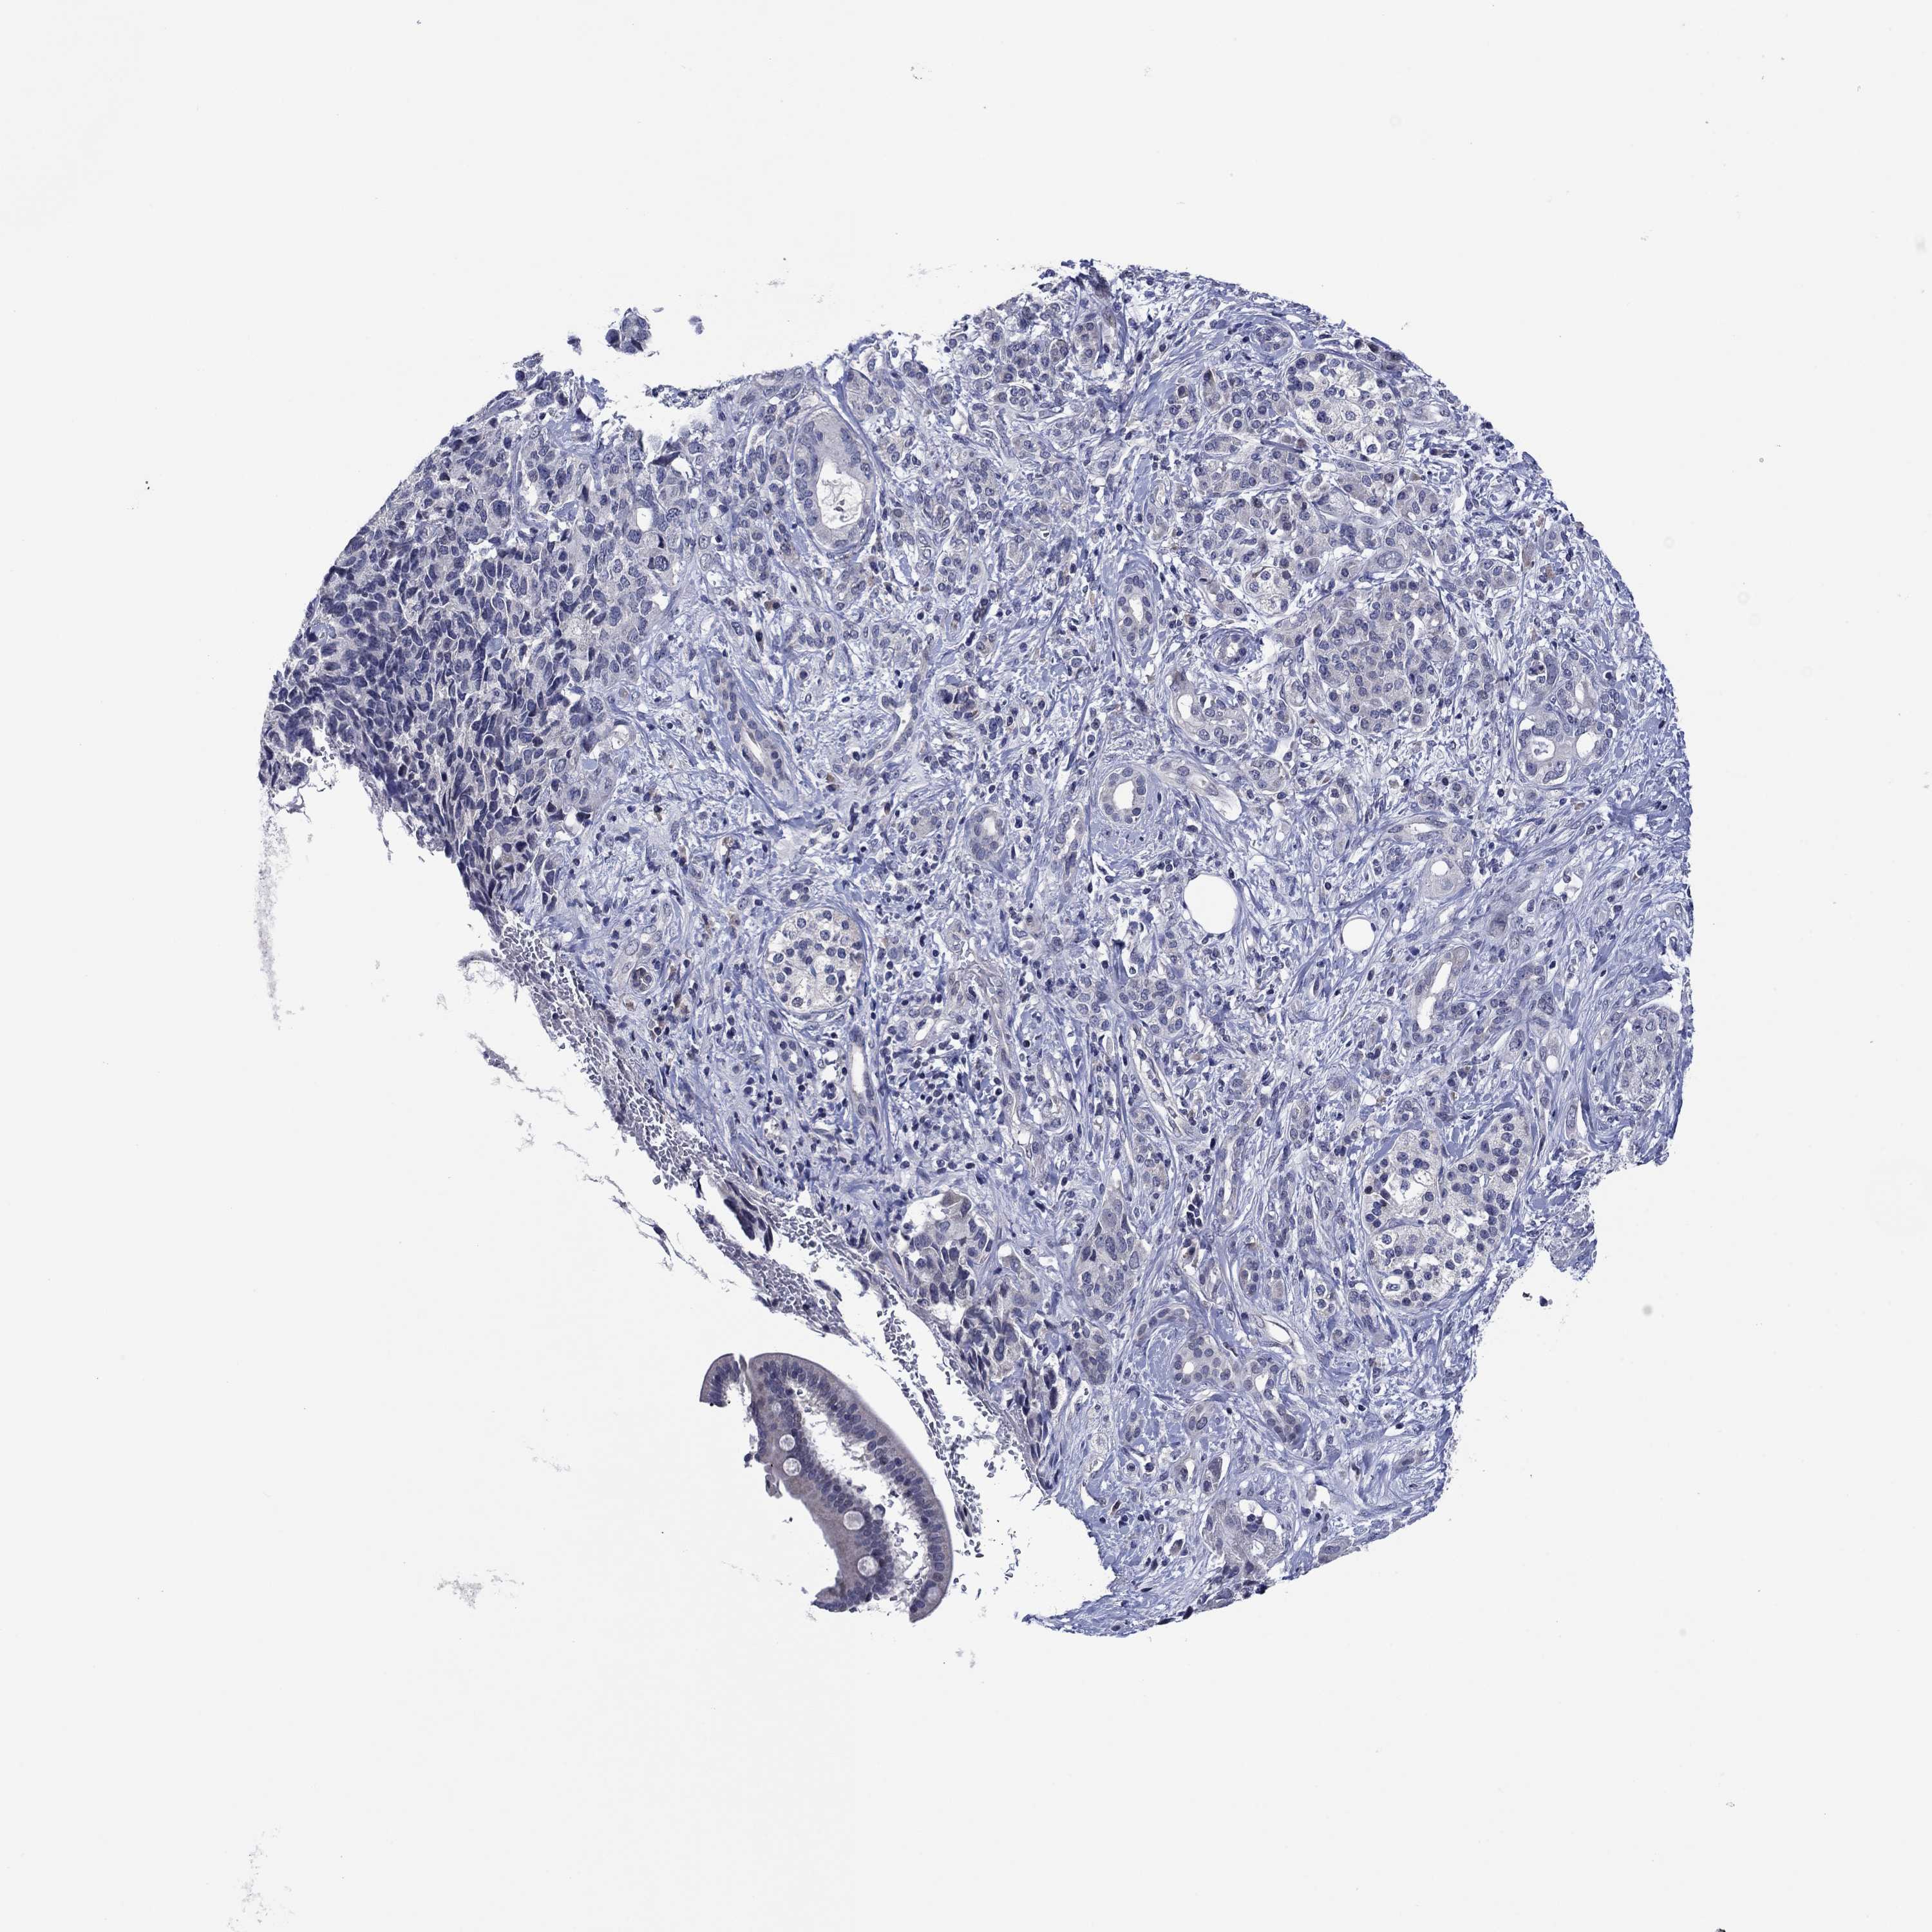

PANCREATIC CANCER - Protein expressioni

A mouse-over function shows sample information and annotation data. Click on an image to view it in a full screen mode. Samples can be filtered based on level of antibody staining by selecting one or several of the following categories: high, medium, low and not detected. The assay and annotation is described here.

Note that samples used for immunohistochemistry by the Human Protein Atlas do not correspond to samples in the TCGA dataset.

Antibody stainingi

Antibody staining in the annotated cell types in the current human tissue is reported as not detected, low, medium, or high, based on conventional immunohistochemistry profiling in selected tissues. This score is based on the combination of the staining intensity and fraction of stained cells.

Each image is clickable and will lead to virtual microscopy that enables deeper exploration of all samples and also displays staining intensity scores, fraction scores and subcellular localization as well as patient and tissue information for each sample.

Antibody CAB078469

Staining

High

Medium

Low

Not detected

Intensity

Strong

Moderate

Weak

Negative

Quantity

>75%

75%-25%

<25%

None

Location

Nuclear

Cytoplasmic/membranous

Cytoplasmic/membranous,nuclear

Adenocarcinoma, NOS